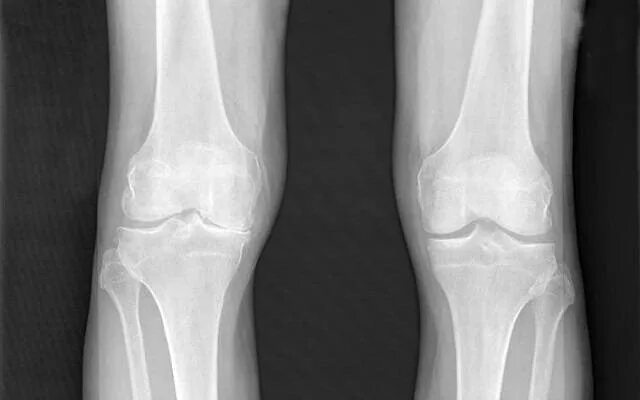

Деформирующий артроз коленных